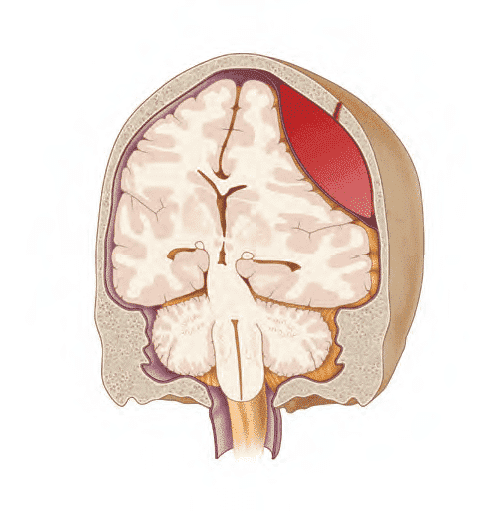

Вогнищеві ураження включають епідуральні гематоми, субдуральні гематоми, забої та внутрішньомозкові гематоми (рис. 6–7).

Рис. 6–7. КТ внутрішньочерепних гематом.

А. Епідуральна гематома.

В Субдуральна гематома.

С. Двосторонні забої з крововиливами.

D. Інтрапаренхімальний крововилив справа із зсувом серединної лінії справа наліво та вторинні бівентрикулярні крововиливи.